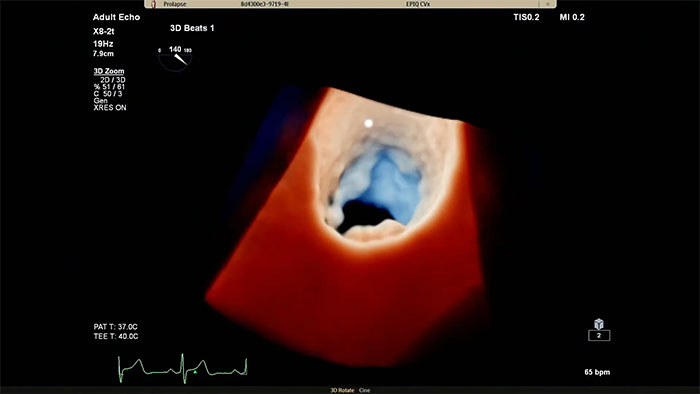

仮想光源によるフォトリアリスティックな3D画像 心臓組織用 TrueVue と仮想光源により、欠損部位や構造の奥行きの把握が容易になり、経胸腔の心臓組織および経食道エコーの視覚化も向上します。新型 EPIQ CVx Transcend を見た臨床医の 90%⁵が、新しい TrueVue 3D フォトリアリスティックレンダリングにより組織構造がより理解しやすく表示されるため、臨床的確信を強く持つことができると回答しました。

僧帽弁疾患の理解を深めるには EPIQ CVx Transcend の Philips Cardiac TrueVue について

インターベンションとのコラボレーション用に開発されたフォトリアリスティックレンダリング 循環器用 TrueVue は、仮想光源を使用してデバイスの視認性を向上させる、新しい 3D 超音波表示方法です。TrueVue は、組織の詳細と奥行き方向の情報を分かりやすく示す画像を提供して、カテーテルおよびデバイスの位置の把握を容易にします。エコー画像がより分かりやすく表示されることで、インターベンション医は確信を持って処置を行うことができます。新型 EPIQ CVx Transcend を見た臨床医の 90%⁵が、新しい TrueVue 3D フォトリアリスティックレンダリングにより組織構造の表示が改善されるため、臨床的確信を強く持つことができると回答しました²。

インターベンションとのコラボレーション用に開発されたフォトリアリスティックレンダリング

循環器用 TrueVue は、仮想光源を使用してインターベンションデバイスの視覚化を強化する、独自の最新 3D 超音波表示方法です。TrueVue は、組織の詳細と奥行き方向の情報を分かりやすく示す画像を提供して、カテーテルおよびデバイスの位置の把握を容易にします。EPIQ CVx Transcend を見た臨床医の 90%⁵が、新しい TrueVue 3D フォトリアリスティックレンダリングにより組織構造の表示が改善されるため、臨床的確信を強く持つことができると回答しました²。